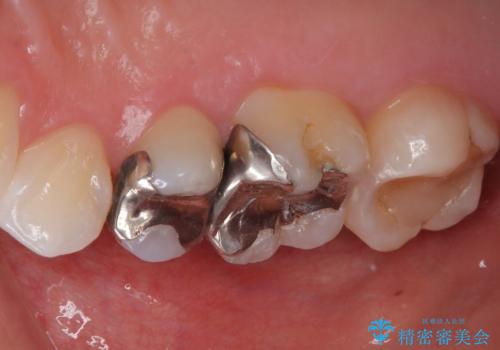

- 銀歯をやり替えたいとのことで来院された患者様です。金属の詰め物の大きさ、虫歯の範囲を考慮してセラミックの詰め物(セラミックインレー)で治療を行っていくことにしました。

拡大鏡視野下で、金属の詰め物(メタルインレー)、虫歯の除去を行い、セラミックインレーに適した形に整えました。